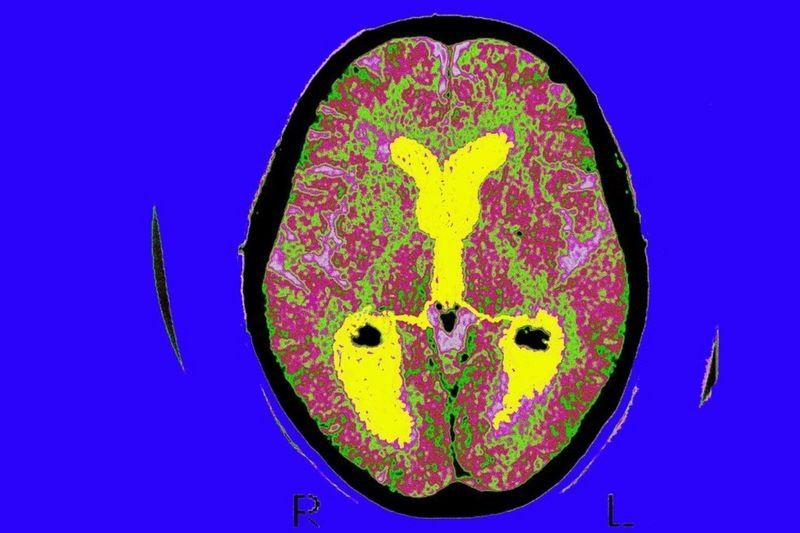

Y es que hemos aprendido muchísimo sobre el funcionamiento del cerebro, sobre todo después de que nuestro compatriota español Santiago Ramón y Cajal descubriera cómo son las neuronas, que son células individuales que se conectan entre sí por contacto, pero no por continuidad, y que eso convierte al cerebro en un órgano inteligente.

Después hay cosas que nos interesan más desde un punto de vista filosófico o que nos interesan más a los científicos, como cómo las neuronas hacen posible la consciencia, la subjetividad o la imaginación.